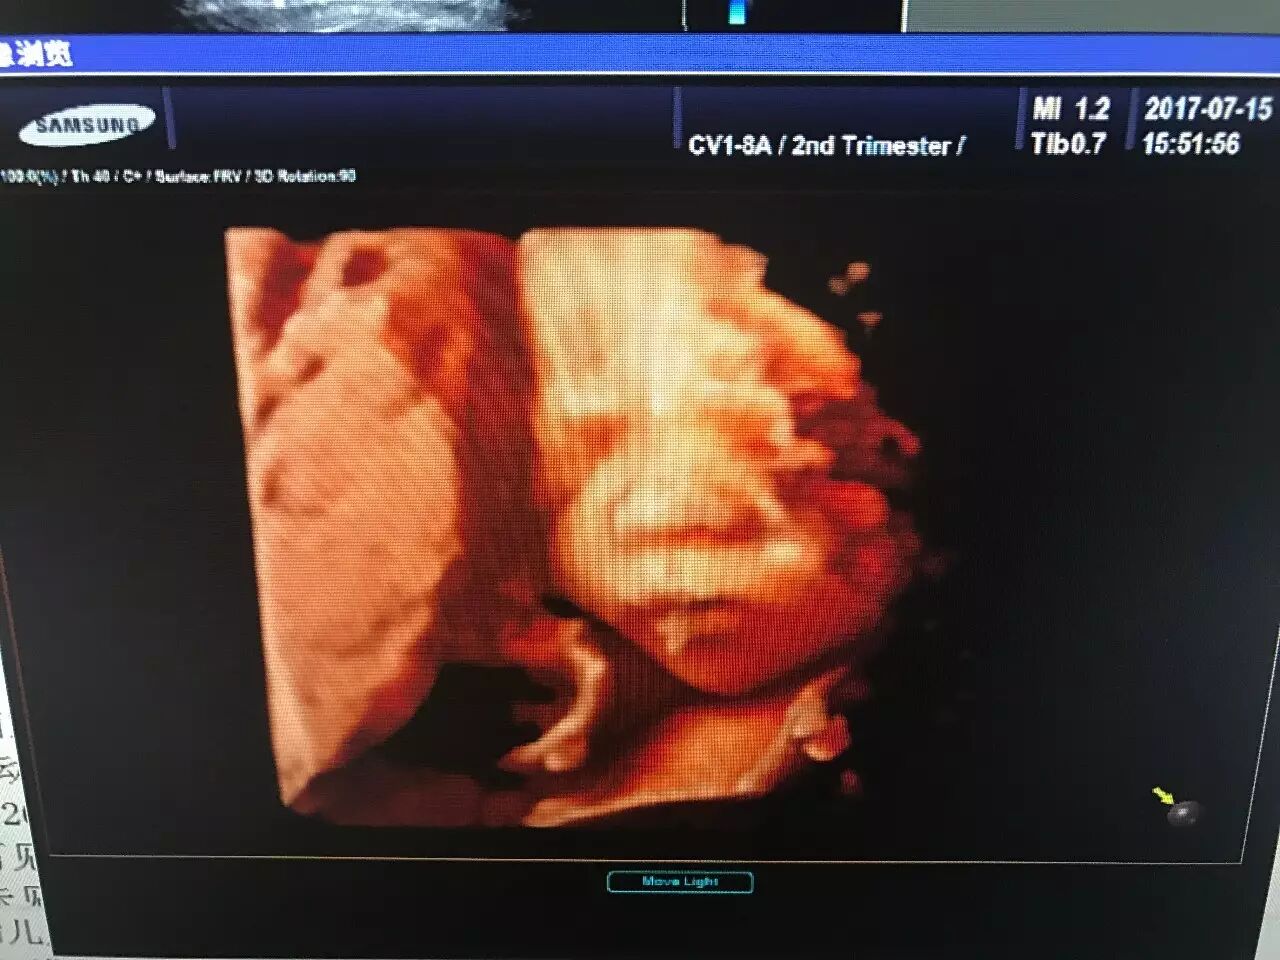

爸爸妈妈用仁德医院的超高端四维彩超

看到的我是酱紫的

(图片来自仁德医院彩超室)

★四维彩超:“4D”是“四维”的缩写,也被称作实时三维。对于超声学来说,4D超声技术是彩超行业的革命性突破。就像是摄像机所拍摄所拍摄到的画面。看到的是立体图像,能看到胎儿的上下左右前后的情况,能更加准确的看到胎儿的情况。

★超高端四维彩超:是采用4D超声图像加上空间维度参数,获取更加立体、逼真的四维图像,超越了传统灰阶超声的大部分限制。其结果是:能够栩栩如生的显示宝宝在妈妈肚子里的实时动态活动高仿真图像,精准排查胎儿畸形。